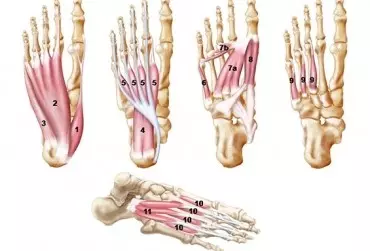

Zastosowanie foot core system

Z całą pewnością można powiedzieć, że stopa jest fenomenem anatomiczno-biomechanicznym, biorąc od uwagę jej złożoną funkcję i budowę. Stopa podobnie jak ręka jest ostatnim ogniwem otwartego łańcucha kinematycznego, jednak pracuje ona w łańcuchu zarówno otwartym, jak i zamkniętym, co już świadczy o jej wyjątkowości. Musi być stabilna, by przenosić ogromne obciążenia, a także mobilna w celu przystosowania się do nierówności podłoża. Stanowi fundament podporu i lokomocji.